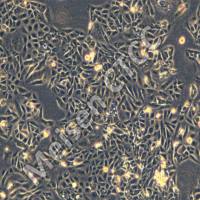

细胞名称:3dGRO® Pancreatic Organoids (OCIP.335)

特点和优势:Cryopreserved patient derived pancreatic cancer organoids (PDOs)

类器官分化流程。人结肠类器官可以通过定形内胚层、后肠内胚层和结肠类器官扩增阶段,使用三步分化方案从人 iPS 细胞生成。 SCM302:定形内胚层诱导培养基,SCM303:后肠诱导培养基,SCM304:3dGRO™ 人结肠类器官扩增培养基 类器官培养方案 步骤1:人 iPS 细胞分化为定形内胚层(第 0-4 天) 注意:起始材料为高品质未分化的人 ES/iPS 细胞(SCC271)(细胞融合度约为 70-80%,且含有 准备单细胞传代培养基。将 ROCK 抑制剂 (ROCKi) Y

在自然界,许多动物拥有着令人惊叹的再生能力,比如「超级选手」海星、蝾螈、斑马鱼(心脏可再生)、扁虫(头部可再生)……科学家们一直希望将这些神奇应用于生命科学,解决器官移植、药物开发等问题。干细胞是组织再生的「源泉」,在此基础之上诞生的「类器官」(organoids)给予了更多的可能。这些在体外培养的微小结构,可以模拟人体器官的复杂结构,还可以重塑体内肿瘤组织的关键特性,有着代替动物试验、实现器官移植的巨大潜力。类器官的获得与治疗潜能01 助力精准医学的「秘密武器」自 2000 年代末,生物